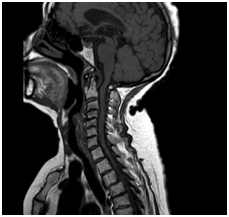

Mr képet spondylosis, extrudált lemez C3-C4, C4-C5, C5-C6, C6-C7.